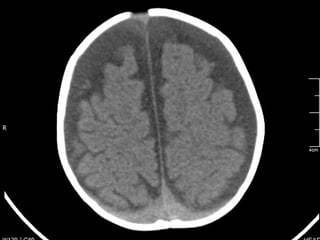

Evolución clínica A los siete meses: TAC craneal: Hematomas subdurales bilaterales. Efecto masa Trépanos bilaterales con evacuación  Colocación de drenajes bilaterales 10 meses: Asintomático. Desarrollo psicomotor normal

Evolución clínica Alos siete meses: TAC craneal: Hematomas subdurales bilaterales. Efecto masa Trépanos bilaterales con evacuación Colocación de drenajes bilaterales 10 meses: Asintomático. Desarrollo psicomotor normal

• #8 Fosa craneal media: hematoma subdural agudo TEMPORAL bilateraL. Fosa posterior: aumento de los espacios que contienen LCR. No hay sangre en fosa posterior

• #9 Hematoma frontal bilateral, mayor izquierdo.

• #10 Aumento del LCR : cisura interhemisférica. Hematoma frontal bilateral AGUDO-SUBAGUDO

• #11 Ventriculomegalia aumento de tamaño de ventrículos laterales. Hematoma subagudo bilateral frontal (menos denso que el parietal pero de mayor densidad que el LCR)

• #12 Hematoma parietal bilateral agudo (sangre hiperdensa). Aumento del espacio interhemisférica